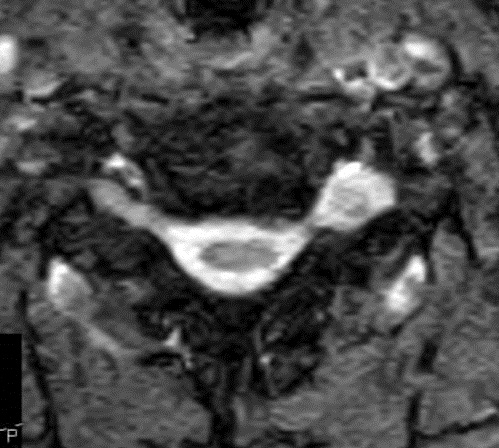

I have provided some select images from the MRI study that was obtained. Initially, the study was ordered non-contrast. Fig. 1 is a midline T-2 weighted image. It demonstrates a degree of posterior disc bulging at C6-C7. No focal posterior discal prominence was noted that would indicate a herniation. Fig. 2 is a gradient echo weighted image through the C6-C7 disc space. In this image, there is obvious expansion of the left intervertebral foramen with a degree of erosion of the facet at the posterior margin of the foramen. The signal intensity is bright on this image, compared to the normal intermediate signal intensity noted within the right foramen. You will note a degree of irregularity at the posterior margin of the disc in this cut, consistent with the disc bulging seen on the sagittal images. There is not sufficient encroachment of the central canal however to account for a neurologic deficit. A left parasagittal STIR image (Fig.3) reveals an obvious focus of abnormal signal within the left C6-C7 IVF that corresponds to the finding that was noted on the axial image. The signal intensity of this area was high on the STIR, gradient echo, and T-2 weighted images, and low on the T1 weighted images, consistent with fluid. At this point what diagnoses would you entertain, and would you order any follow-up imaging or testing?